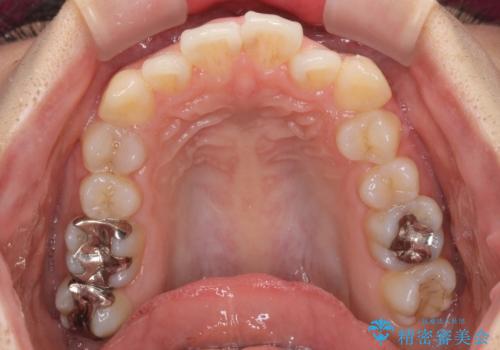

右上の小臼歯は歯根癒着をしており、様々な方法を試みるも動かすことができませんでした。

それでも奥歯のかみ合わせに不自由はなく、歯列をきれいに整えることができました。